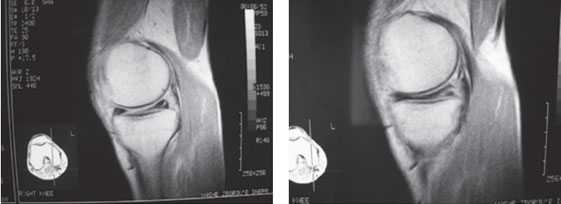

На ранних стадиях заболевания, при незначительных изменениях в костной ткани, рентгенологическое обследование не настолько ценно. [5] [8] На этом этапе гонартроз возможно диагностировать благодаря артроскопии. [5] [8] Точность метода очень высока, останавливать может только его инвазивный характер и цена.

УЗИ не позволяет произвести четкую визуализацию изменений суставного хряща и внутрисуставных структур. [15] С помощью МРТ можно с 85% точностью выявить изменения костных, хрящевых и мягкотканых структур сустава, а также субхондральной кости. [15] С помощью сцинтиграфии можно оценить метаболическую активность периартикулярной костной ткани.